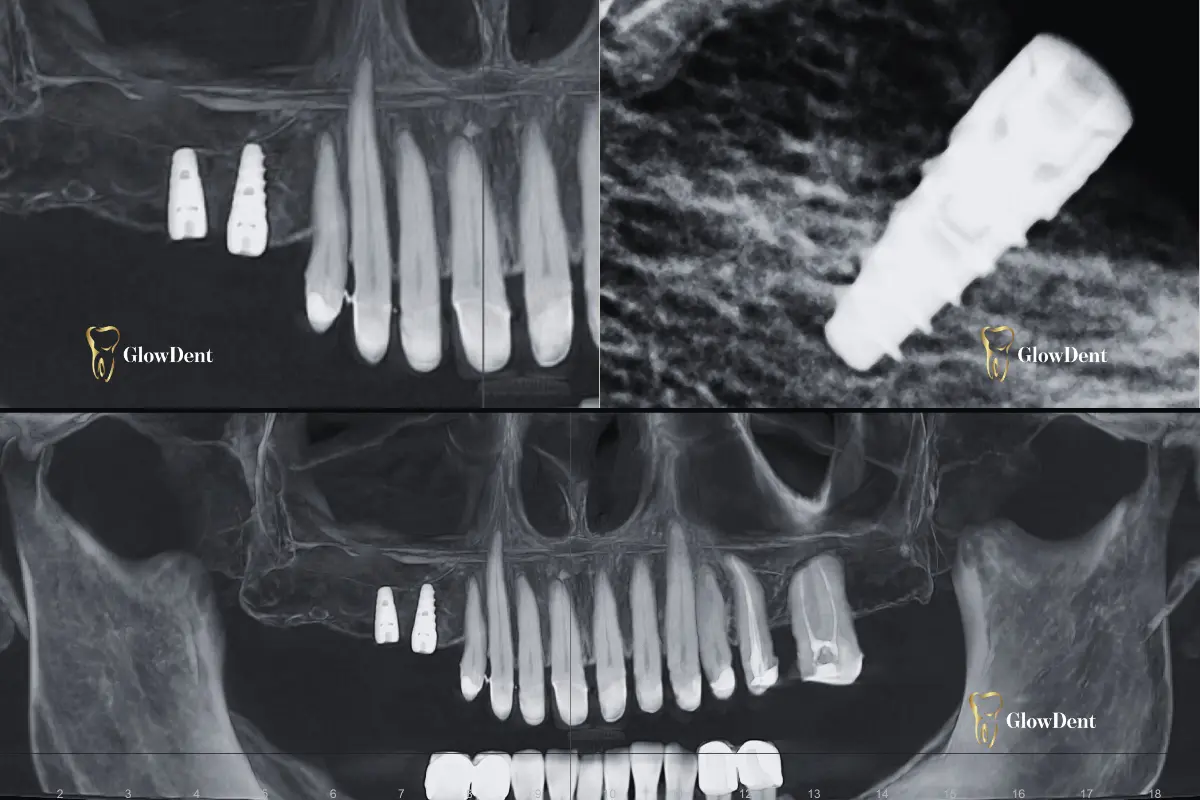

Zubni implantati su titanijumski vijci koji se ugrađuju u kost vilice i preuzimaju funkciju korijena izgubljenog zuba. Na njih se postavlja krunica, most ili proteza, u zavisnosti od stanja pacijenta.

Kao savremena stomatološka ordinacija s fokusom na implantoprotetiku, naš tim u GlowDent – u pruža maksimalnu posvećenost svakom pacijentu. Koristimo premium implantate, radimo uz preciznu 3D dijagnostiku, a svi zahvati se obavljaju bezbolno i stručno.